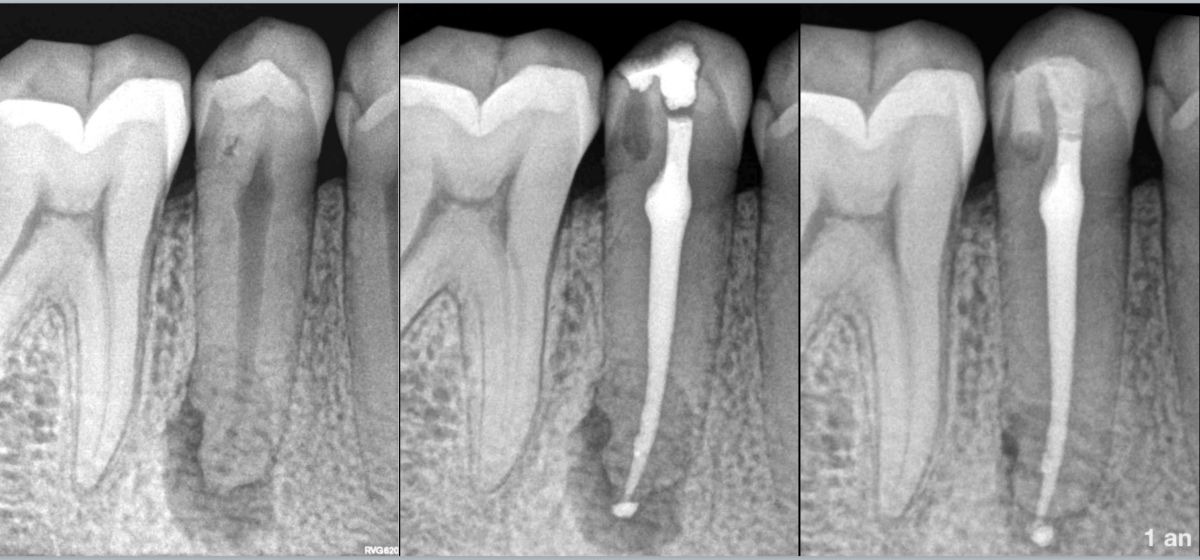

🦷 Pulpe nécrosée

🧐 Parodontite apicale asymptomatique

🌀 Dens invaginatus